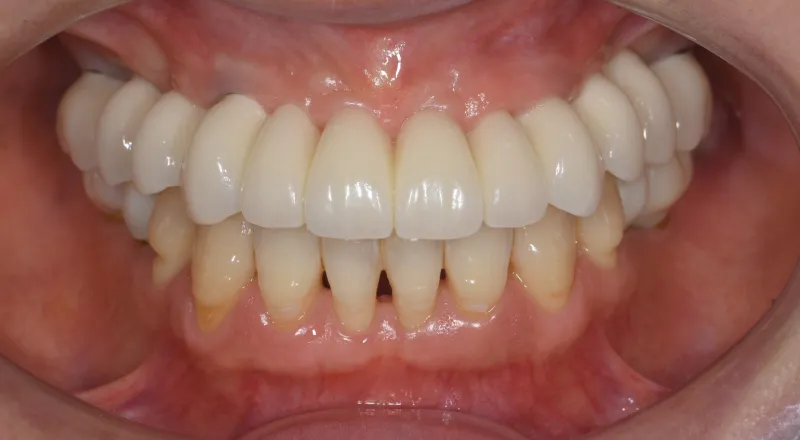

| 主訴 | 歯が抜けている。 入れ歯のところをインプラントしたい |

|---|---|

| 診断名 | 歯の欠損、義歯不適合 |

| 年齢・性別 | 63歳・男性 |

| 治療期間・回数 | 1年3ヶ月・33回 |

| 治療方法 | 精密根管治療、ジルコニアクラウン、GBR、インプラント、ホワイトニング |

| 費用 | 3,949,000円 最高プラン (費用を抑えたプランも提案可能) |

| 治療上のリスク |

|